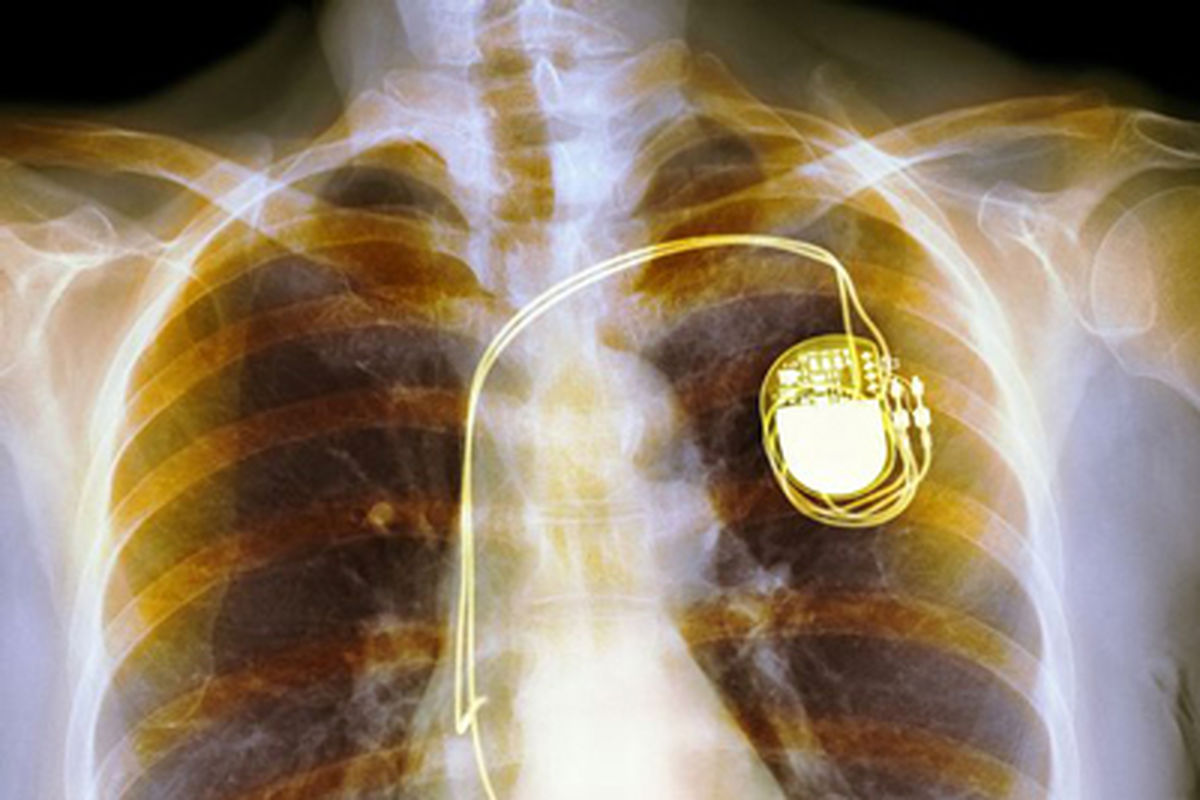

راه اندازی خدمت آنالیز پیس میکر (باطری) قلب در مجتمع آموزشی، پژوهشی و درمانی شهید محمدی

رئیس مرکز آموزشی ، پژوهشی و درمانی پیامبر اعظم(ص) بندرعباس از راهاندازی بخش خدمت آنالیز پیس میکر (باطری)قلب در این مجتمع درمانی خبر داد.

به گزارش خبرگزاری برنا هرمزگان، عبدالله غریب زاده رئیس مرکز آموزشی، پژوهشی و درمانی پیامبر اعظم (ص) بندرعباس، اظهارداشت: با پیگیری گروه قلب بیمارستان شهید محمدی خوشبختانه از این به بعد بیماران دارای پیس میکر قلب با مارک شرکت «سنت جود» و «مدترونیک» میتوانند با مراجعه به بخش قلب بیمارستان، بررسی دوره ای باطری قلب خود را انجام دهند و نیازی به مراجعه به استانهای دیگر ندارند.

وی افزود : در حال پیگیری تامین دستگاه آنالیز شرکتهای «بوستون» و «بیوترونیک» نیز هستیم تا بیمارانی که به دلایل مختلف از این مدل باطری قلب استفاده میکنند برای آنالیز دوره ایی نیازی به مراجعه به استانهای دیگر نداشته باشند .